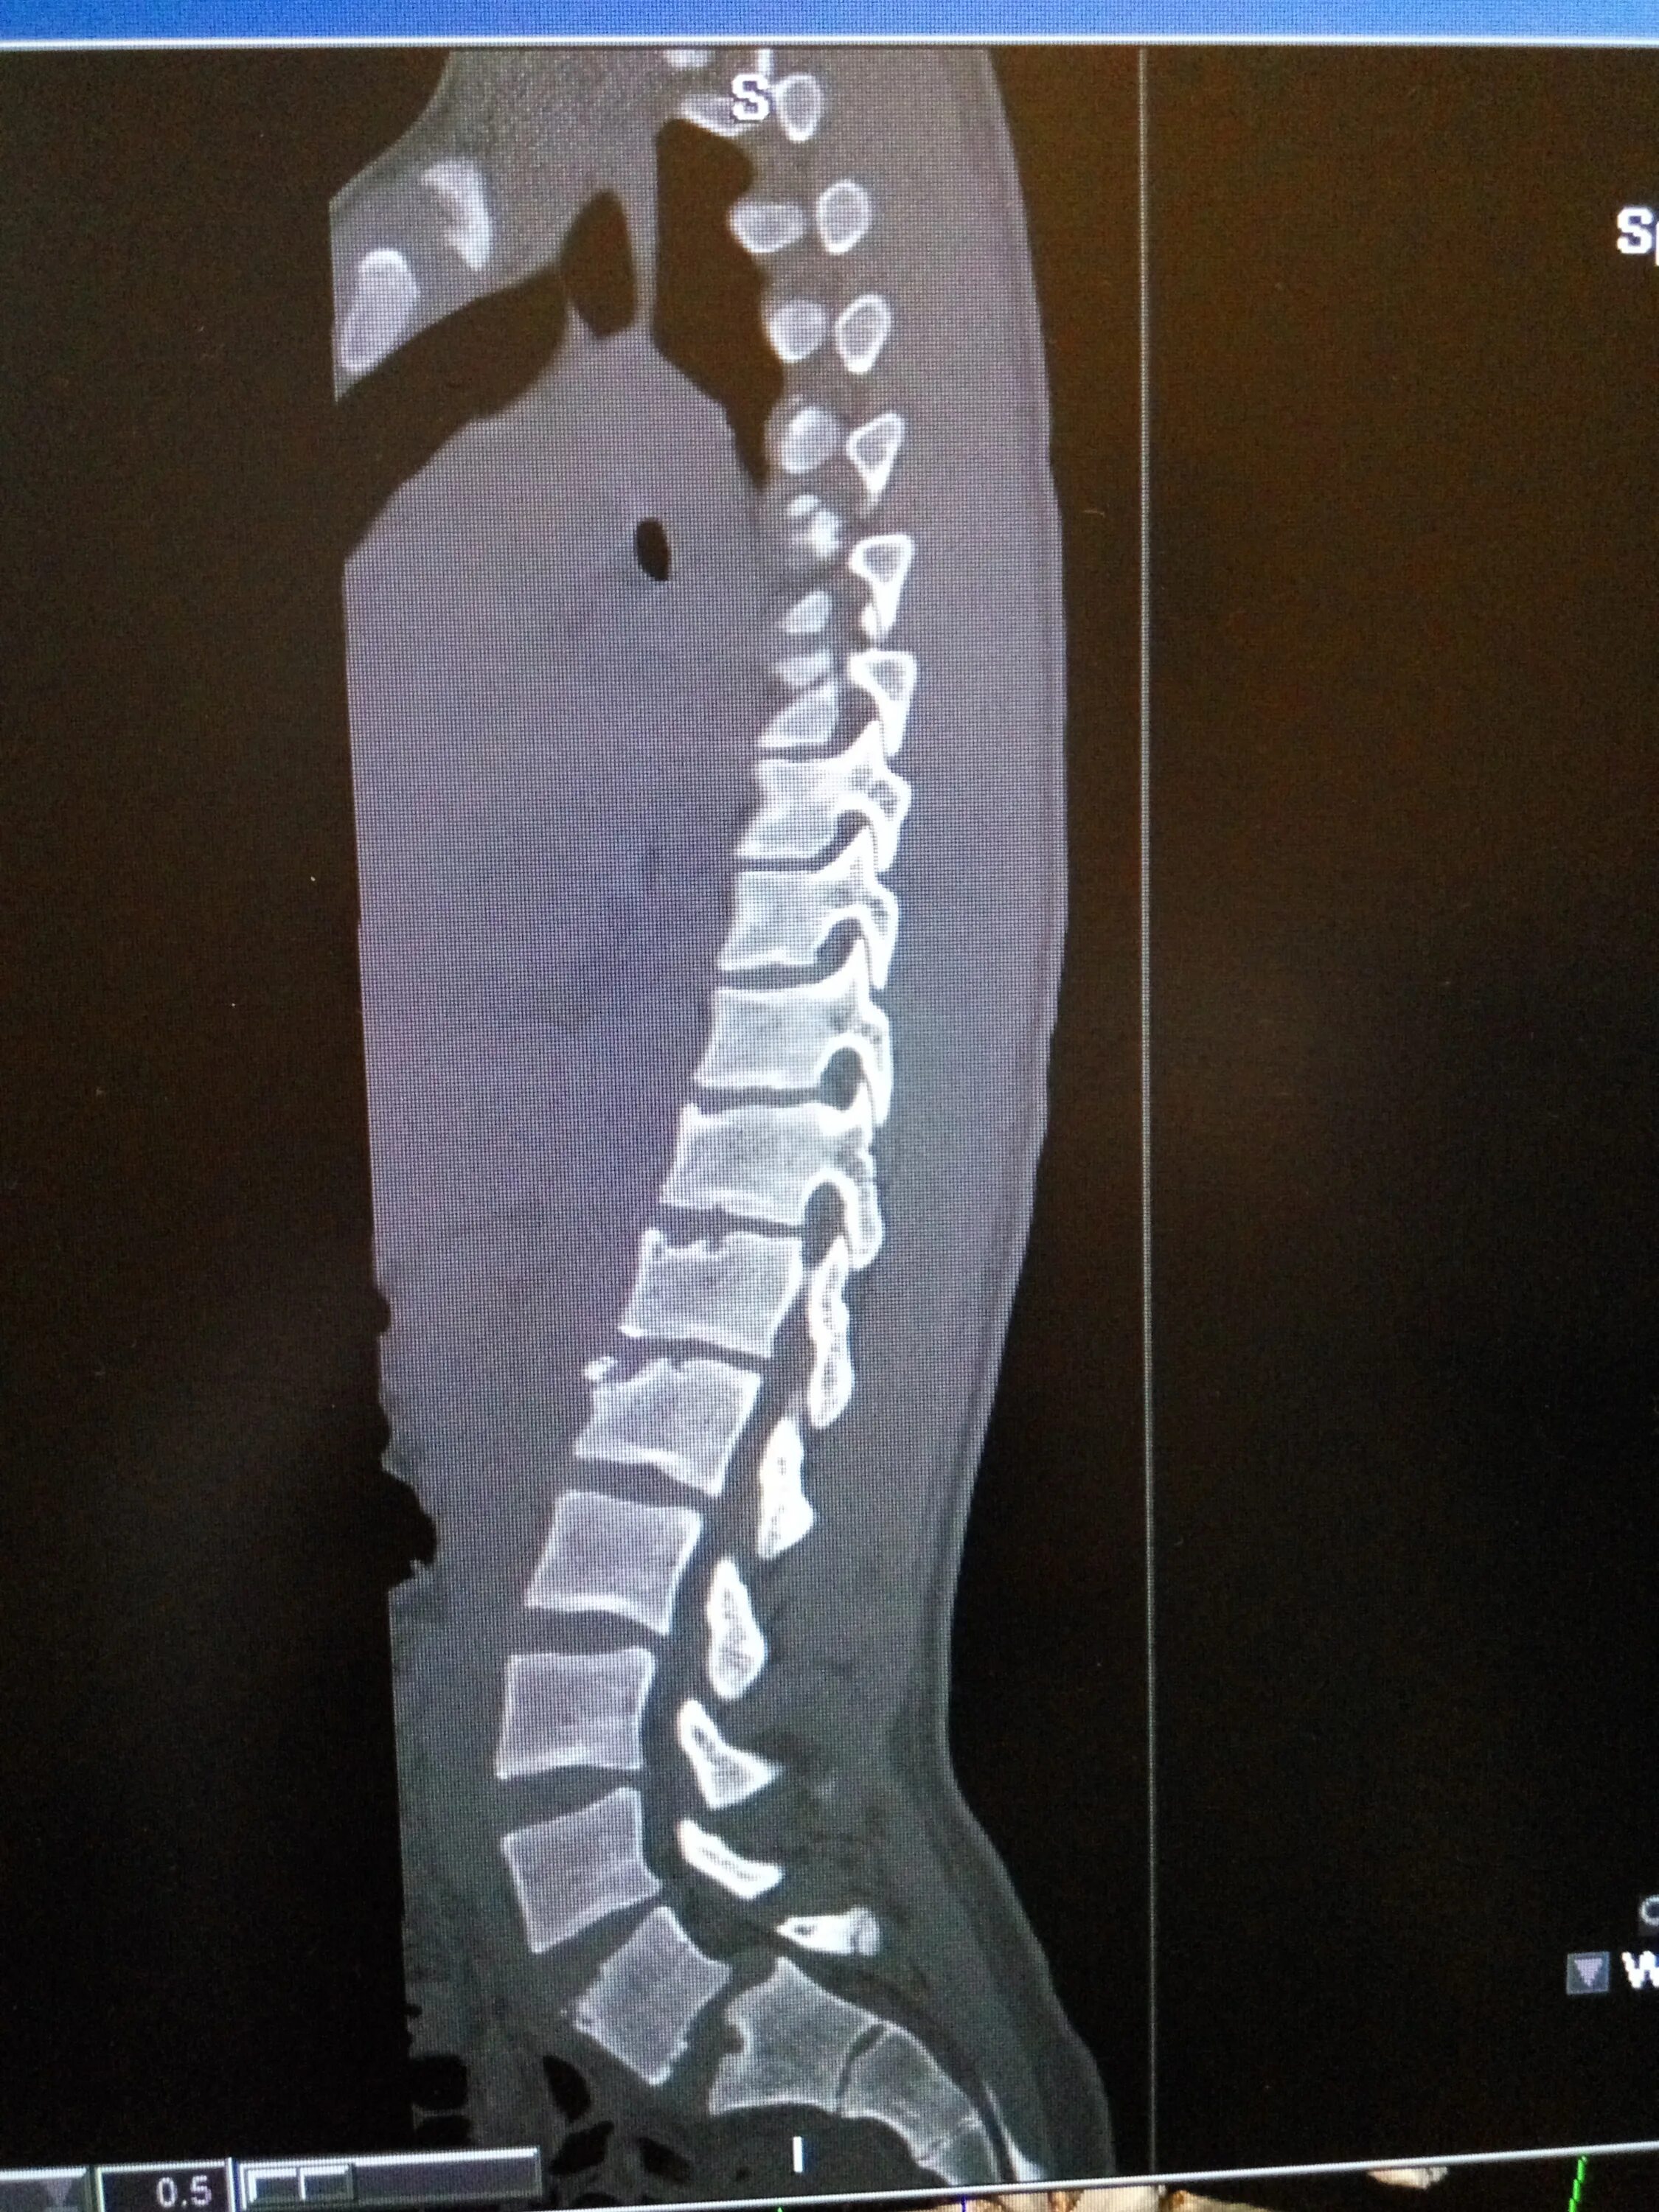

Спондилодисцит мкб